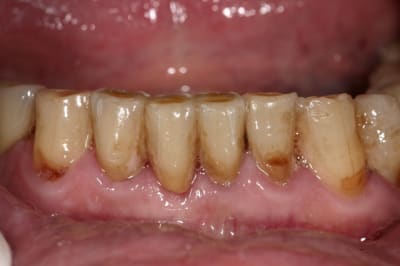

Img 9330 juy6ml - Eugenol

Img 9333 iony5e - Eugenol

Img 9695 sm9nk3 - Eugenol

Img 8465 fqhxid - Eugenol

J'aime vraiment ton boulot. Superbe !

tres beau travail de ceramique chapeau au prothesiste.

Nouvelle céram, saveur nicotine ?

;) disons teinte locale :)

Disons que plus la teinte est moche et foncée plus le prothésiste peut se lacher facilement

juste une remarque;

sur la photo (sur la photo uniquement) on devine un aspect de surface très légèrement granuleux parrapport à celui des dents voisines.

ceux sont des minuscules bulles qui sortent lors de la dernière cuisson, pour éviter cela tu dois polir toi même (comme ça c'est sure que c'est fait) ton biscuit. tu verra, le résulta n'en sera qu'encore meilleur.